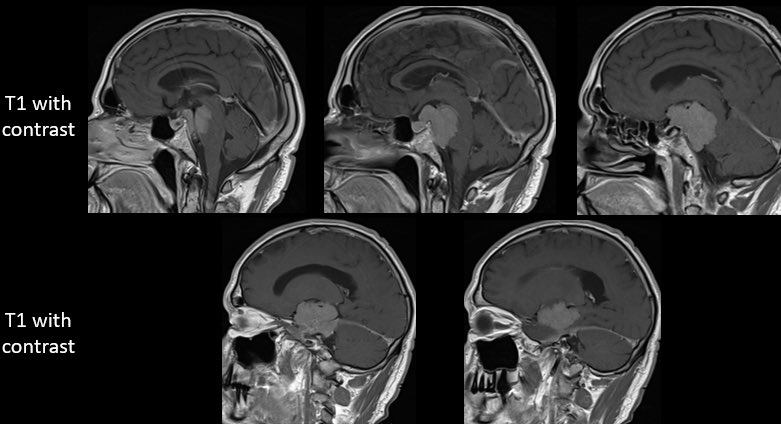

How would you manage this 42F w/ intracranial recurrence of optic nerve sheath meningioma initially biopsied at OSH 5 yrs ago. R eye blind, L 20/20, EOMI. Observation? Radiation? If surgery, approach/extent of resection? #Neurosurgery #MedEd #MedTwitter @EvaWuMD @TheJNS @WFNSHQ